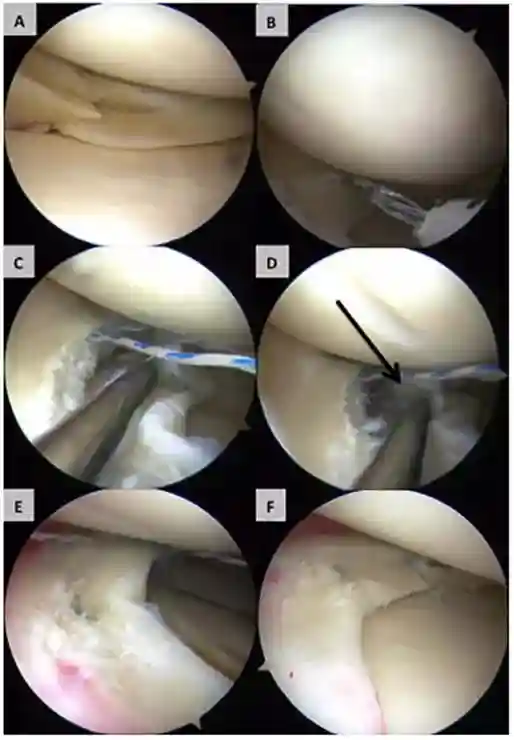

2016年英国布里斯托尔大学的迈克尔.怀特豪斯博士()所在的研究小组对5例无血管半月板损伤患者进行干细胞为手段的治疗,自体骨髓MSCs接种在胶原包被的支架上,人MSCs-胶原-支架被移植到5例患者的半月板损伤处。追踪随访24个月后,发现上述患者症状均得到显著性改善,其中3例症状消失,半月板损伤彻底治愈,而另外2例由于移植15个月后损伤症状仍未得到改善,需要接受后续半月板切除手术,但几个患者均未发生不良反应[20]。

图解(一位患者的术中关节镜图像显示的人间充质干细胞的植入方法)

(图b术后3个月;图c术后6个月;图d术后12个月;图e术后24个月)